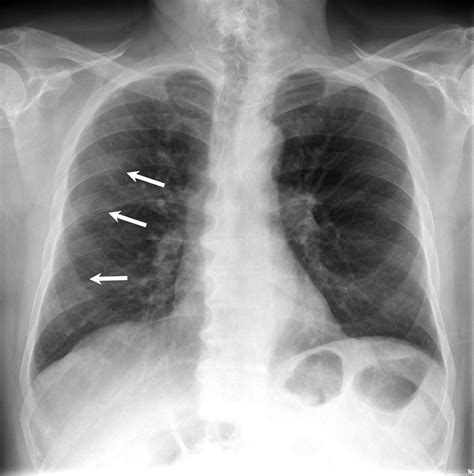

• Focal GGO: A localized area confined to one spot.

• Fluid Accumulation: Pulmonary edema, often caused by heart failure, can result in hazy lung appearances due to fluid filling the tiny air sacs.

• Chronic Lung Diseases: Conditions such as interstitial lung disease (ILD) or idiopathic pulmonary fibrosis can manifest as persistent ground glass shadows.